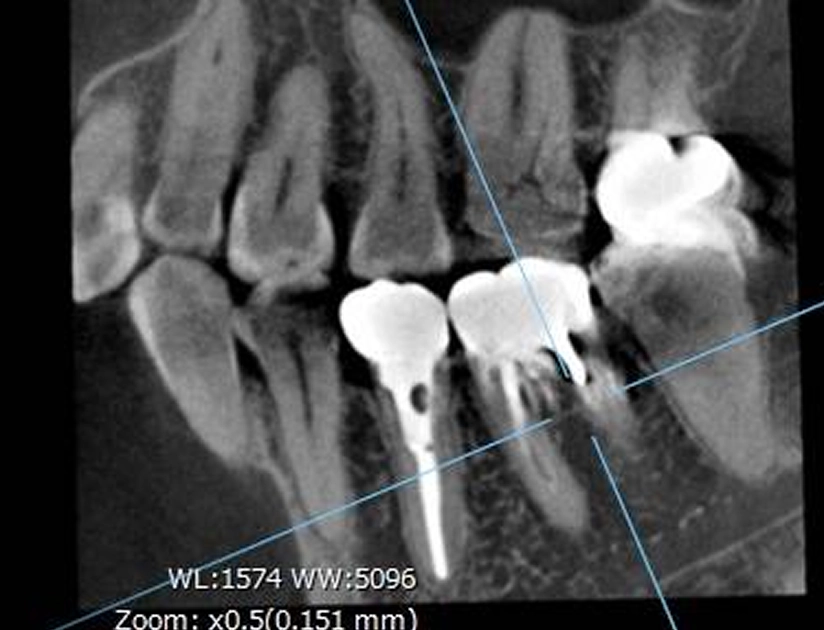

CTによる精密分析

CT撮影を行うことで、根管の形や方向、周囲の骨の状態を立体的に把握します。難しい症例や再治療の場合にも、安全で的確な処置を行うための重要な検査です。